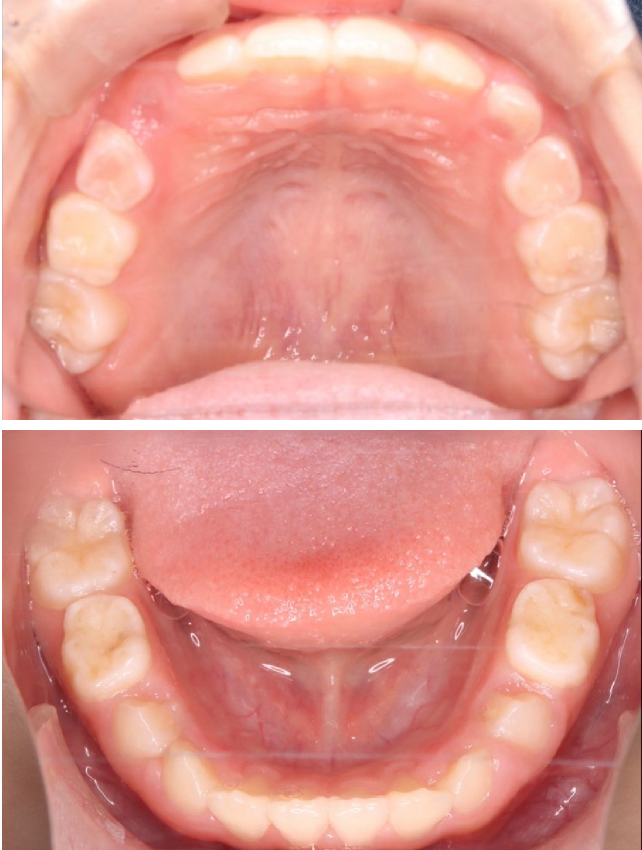

当院の症例

CASE